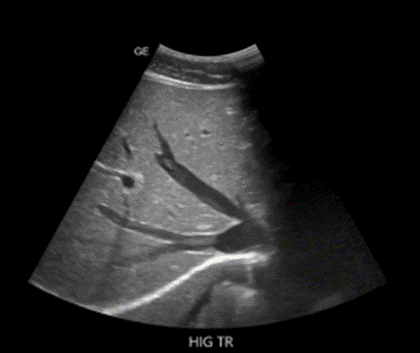

Vesícula parcialmente distendida de paredes edematosas, levemente engrosadas, presenta tenue señal al power doppler

Hígado: conserva forma, tamaño y contornos regulares. El parénquima se visualiza ecográficamente heterogéneo, con aumento a nivel de la triada portal en cielo estrellado, sin áreas de focalización intraparenquimatosa. El sistema biliar intrahepático luce normal

Vesícula biliar: poco distendida, de paredes engrosadas, sin ecos en su interior